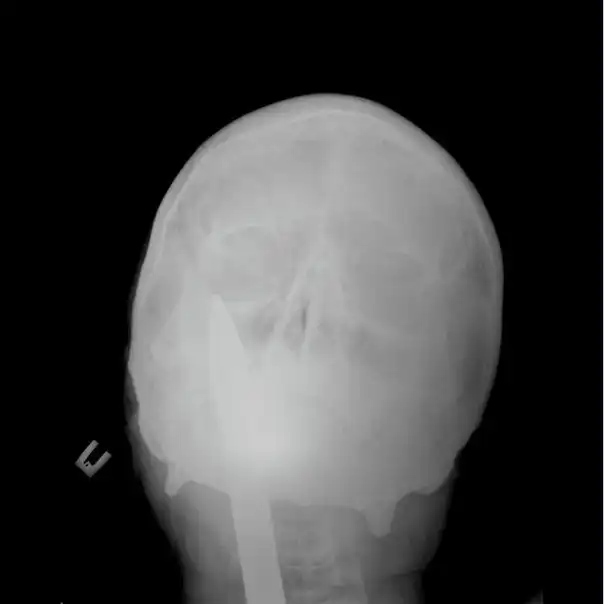

Мужчина упал на лом не повредив жизненно важных органов, говорят после операции выписан в удовлетворительном состоянии домой.

Счастливчик 80 уровня, на снимках и правда видно ни мозг, ни глотку не повредил, везунчик.

Какие ещё оба конца, 3 раза пролистала, то что вы имеете в виду так и не поняла. На всех фотографиях включая рентген пикой внутрь раздвоенной частью наружу.